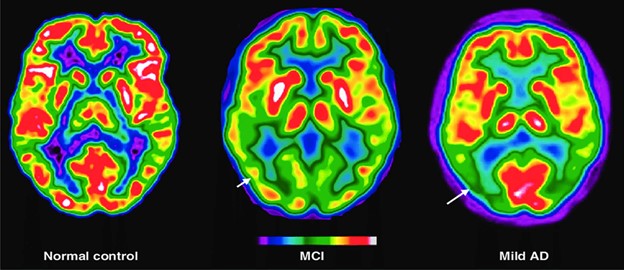

متأسفانه اغلب ما تصور می‌کنیم افزایش سن و پیری دلیل ایجاد بسیاری از بیماری‌های عصبی شناختی مانند آلزایمر یا زوال عقل می‌گردد. اما لازم به ذکر است بنابر پژوهش‌های انجام شده نشانه ابتلا افراد به زوال عقل تنها افزایش سن نیست، بلکه علائم دیگری مانند تغییر خلق‌وخو، عدم توانایی وظایف روزانه، مشکل در ایجاد ارتباط، تکرار حرف‌های پیشین، ناتوانی در یافتن واژه‌ها، کناره‌گیری از فعالیت‌های اجتماعی به‌دلیل تغییرات شخصیتی و ازدست دادن حافظه به‌طوری که اطلاعات به‌دست آمده را به‌سرعت فراموش کنند نیز وجود دارد که در تشخیص این نوع اختلالات باید آن‌ها را نیز درنظر داشت. نشانه‌های اختلالات عصبی شناختی در ابتدا بسیار کم‌رنگ هستند و احتمال دارد دوستان یا خانواده فرد مبتلا اصلاً متوجه آن‌ها نشوند یا آن‌ها را جدی نگیرند. این نشانه‌ها در برخی بیماران ثابت می‌ماند و در برخی رو به وخامت می‌گذارد که در دسته‌ای مبتلایان که به اختلال شناختی خفیف MCI مبتلا هستند به مرور زمان به زمال عقل می‌انجامد.